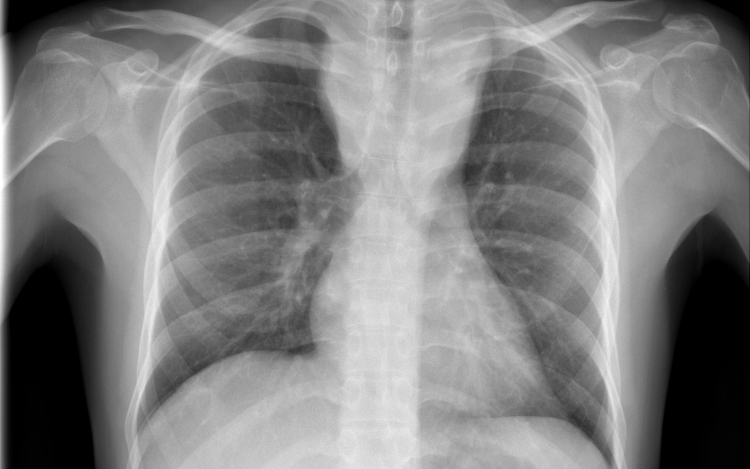

Forrás: mti - illusztráció

Tüdőrákban halt meg egy szervátültetett, aki egy erős dohányos tüdejét kapta meg

Tüdőrákban halt meg a transzplantáció után másfél évvel egy francia nő, akibe egy hajdan erős dohányos nő tüdejét ültették át.

A Lunc Cancer szakfolyóiratban megjelent tanulmány szerint az 57 évesen elhunyt donor 30 éven át napi egy doboz cigarettát szívott el.

A gyermekkora óta cisztás fibrózisban szenvedő páciens 2015 novemberében kapta meg a sokáig erősen dohányzó nő tüdejét, 2017 júniusában pedig bekerült a montpellier-i egyetemi klinikára, ahol két hónappal később elhunyt tüdőrákban, anélkül, hogy bármiféle terápiát alkalmazhattak volna nála. A tanulmány szerint a páciens a dohányzás okozta tüdőrák jellegzetes tüneteit mutatta.

A transzplantáció és a tüdő első rendellenességeinek röntgen általi észlelése közti rövid idő arra utal, hogy a tüdőrák már a donornál keletkezett, a szervkilökődés megakadályozására szedett immungyengítő gyógyszerek pedig csak felgyorsították a kifejlődését.

A tüdőrák hosszú lappangási idejére tekintettel a kutatók különleges elővigyázatosságot ajánlanak a dohányzó donoroktól származó szervek átültetésénél olyan esetekben, amikor a donor csak nem sokkal a transzplantáció előtt hagyott fel a dohányzással.